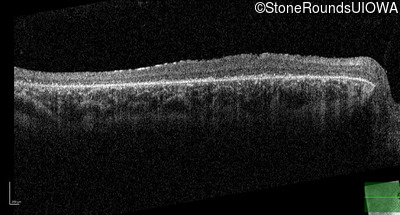

Optical Coherence Tomography - Left - 20/100 -2 sc

Exemplar / OCT Stack

OCT Stack